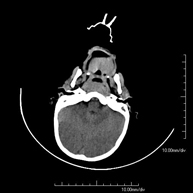

- TC Cráneo

Prueba radiológica que consiste en obtener imágenes del cráneo de alta definición anatómica (tronco cerebral, cerebelo, cerebro, calota craneal, etc.), mediante el empleo de un equipo de TC (Tomografía Computarizada).Indicaciones: traumatismos, cefalea, trastornos de la memoria, pérdida de fuerza súbita en una extremidad o mitad del cuerpo. - TC Cuello

Prueba radiológica que consiste en obtener imágenes del cráneo de alta definición anatómica mediante el empleo de un equipo de TC (Tomografía Computarizada). Indicaciones: cefalea, estudio de tumores, traumatismo craneal. - TC Cuello